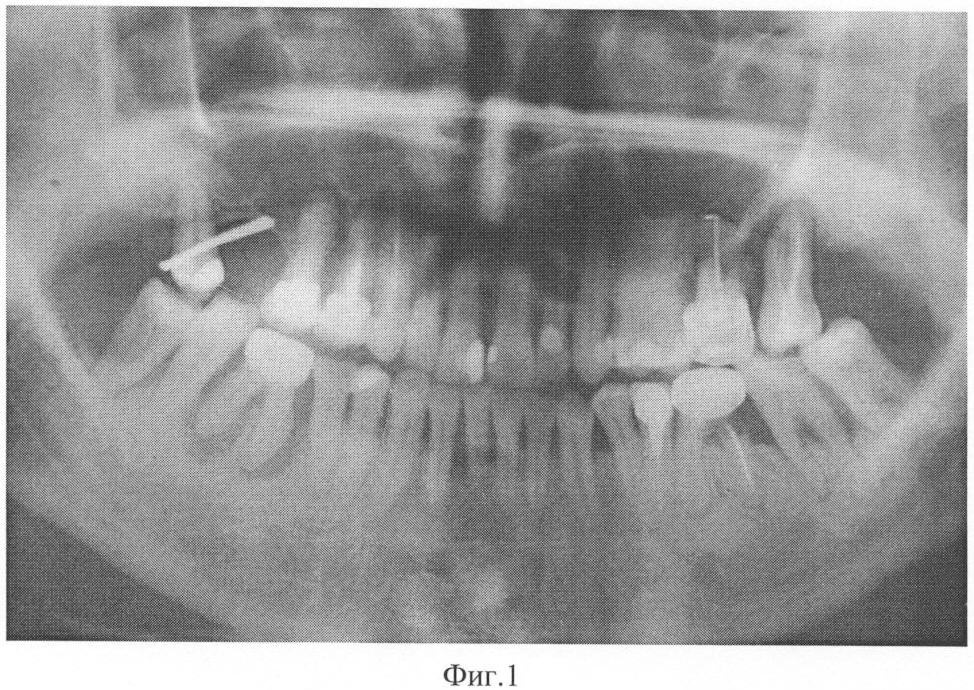

На фиг.3 представлена рентгенограмма пациента 2 до лечения заявленным способом.

Данные рентгенологического исследования. На ортопантомограмме верхней и нижней челюстей определяется убыль костной ткани в области зуба 46 на всю длину корней округлой формы (рентгенологические признаки пародонтальной кисты). В области зуба 36 имеется резорбция костной ткани на 1/2 длины корней.

Диагноз: хронический генерализованный пародонтит тяжелой степени с агрессивным течением.

Больной было проведено комплексное лечение, включающее обучение гигиене полости рта, снятие поддесневых зубных отложений и кюретаж пародонтальных карманов, проведение антибиотикотерапии (сумамед 250 мг – 5 дней), изготовлена балочная шина в области 45, 46, 47. Сразу после проведения хирургического лечения (лоскутная операция с остеопластикой и введением препарата Остеопласт в область вертикальных костных дефектов) был назначен курс препарата Калькохель по одной таблетке три раза в день в течение трех недель, затем препарат Остеохель С по одной таблетке три раза в день в течение трех недель, затем перерыв три недели и повторно те же препараты тем же курсом. Повторное обследование проводили через 11 месяцев после начала лечения. Осмотр полости рта показал следующее: слизистая оболочка десны бледно-розового цвета, без признаков кровоточивости. На ортопантомограмме определяется закрытие вертикальных костных дефектов в области 46 на 1/2 полноценной костной тканью, в области 36 до 1/3.

Данные лабораторных исследований. ПТГ=34,4 пг/мл, кальцитонин 3,9 нг/л, кальций общий 2,48 ммоль/л, кальций ионизированный 1,1 ммоль/л. Сама пациентка отмечает значительное улучшение состояния, исчезновение кровоточивости десен и подвижности зубов, отсутствие рецидивов заболевания более 3 лет. Пример подтверждается рентгенограммами, выполненными до лечения – фиг.3 и после лечения – фиг.4.